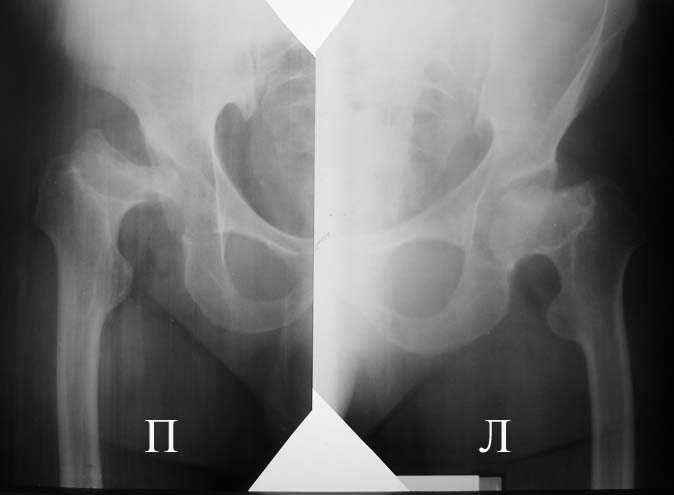

Прямая проекция т/б суставов

Алексей, судя по снимкам, правый тазобедренный сустав нуждается в замене. Думаю, что получится поставить протез без дополнительных конструкций во впадину и особых ножек. Важным является диаметр канала. Надо по шаблонам оценить размер. Самые маленькие из известных мне ножек в России предсталены у De Puy (бесцементная 6), и новинка от BIOMET бесцементная диспластическая ножка.